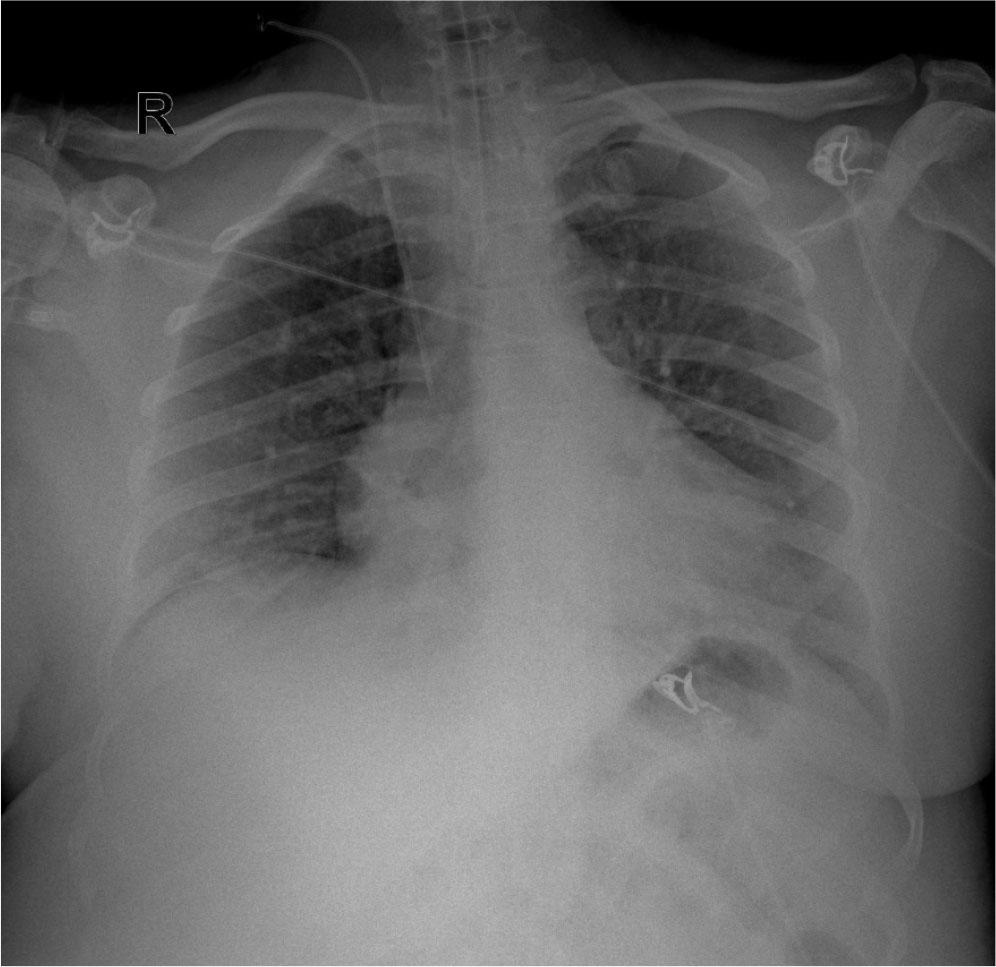

Fig. 1.